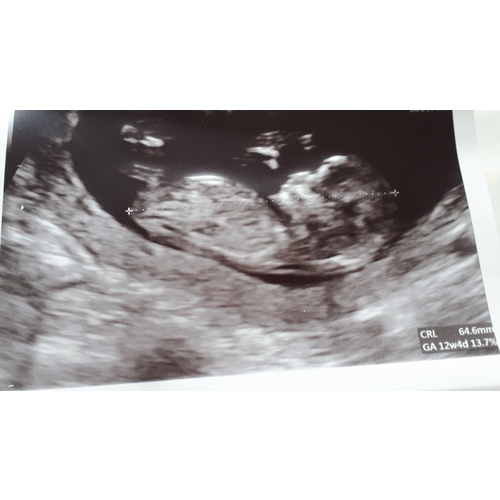

In bijlage zie je onze laatste echo van 12w1d. Wat denken jullie? En is dat nu het befaamde nubstaartje of eerder een stukje bot van iets anders 🤗